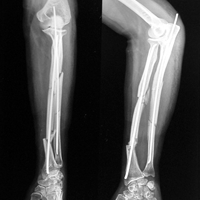

Case:8 Polytrauma

Patient having closed segmented fracture midshaft & lower 1/3 Tibia with closed fracture superior & inferior pubic rami right side with pelvis fracture following vehicular accident wastreated with intramedullary nail for fracture tibia and external fixator for fracture pelvis.

Pre-Op

Immdiate Post-op

Post-op Lateral

Ex fix with frame